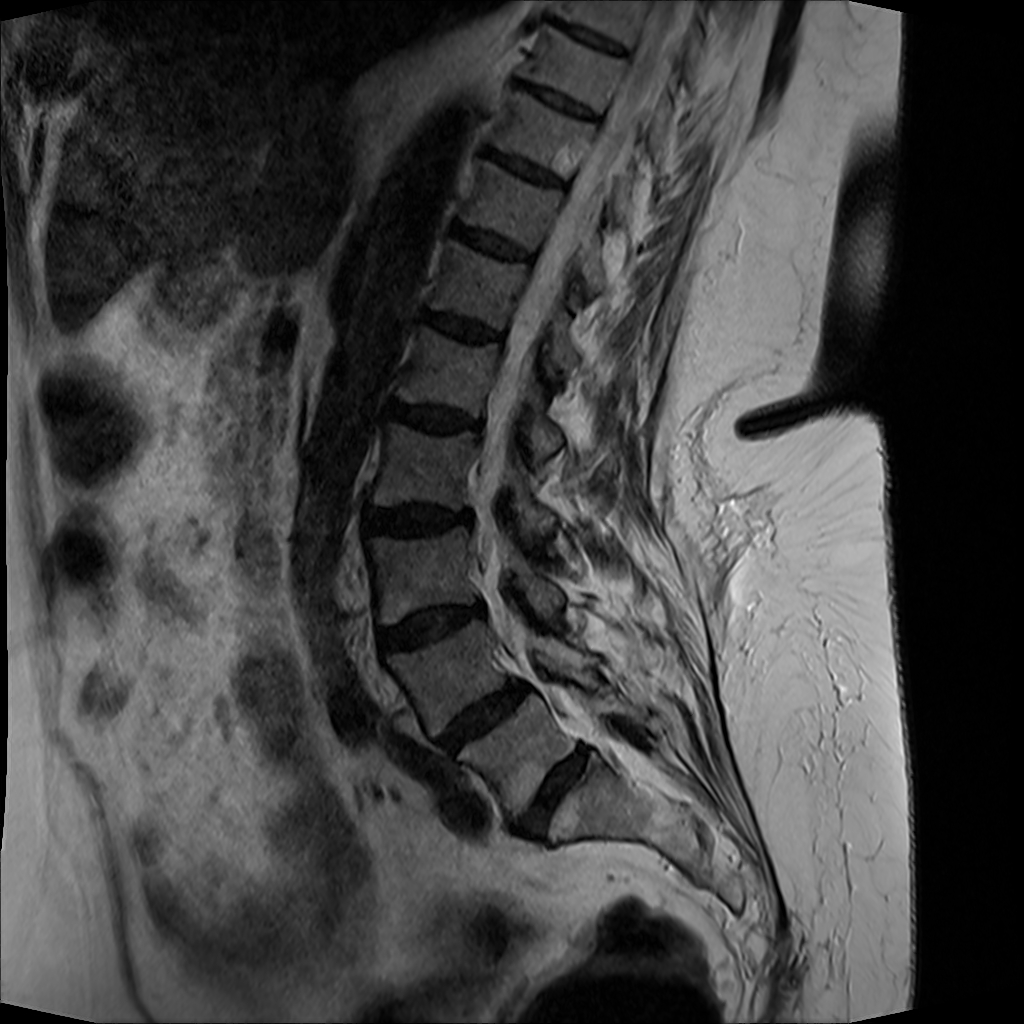

MRT Lendenwirbelsäule + Röntgen Becken - Diagnostik vor OP-Planung

MRT LWS (Lendenwirbelsäule)

DICOM

Magnetresonanztomographie der Lendenwirbelsäule (71 Bilder).

19.01.2024

MRT Lendenwirbelsäule (LWS)

71 Bilder | 1024x1024 px | 15 MB

MRT LWS

71 Bilder

Januar 2024

MRT LWS + Röntgen Becken

MRT der Lendenwirbelsäule und Röntgen des Beckens zur Diagnostik

MRT mit 71 Bildern